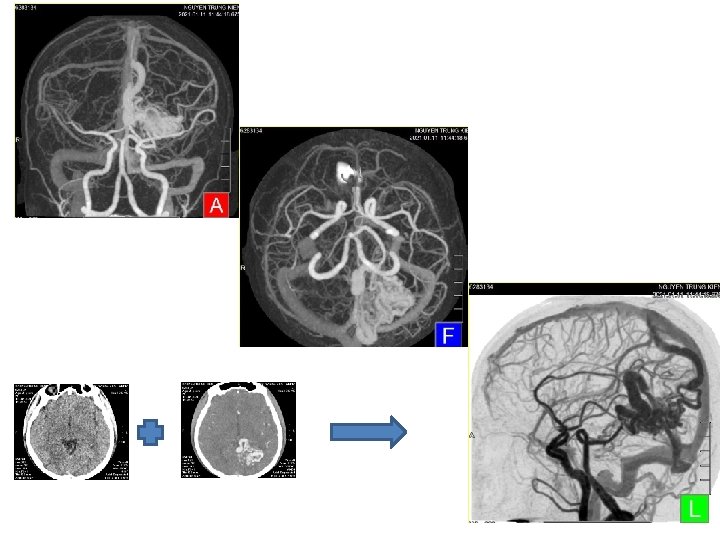

A NUMBER OF CLINICAL APPLICATIONS FOR NEUROLOGICAL CT ANGIOGRAPHY • Cerebral aneurysms — especially close to the bone • Patients with ischemic disease — ICA, basilar artery • Cases with stenosis or occlusion — close to bone • Patients with a clip or coil • Patients with calcification • Patients with hypervascular tumor • Patients scanned from neck to head

CONCLUSION • Subtraction CT angiography is enable noninvasive vascular imaging with fine detail, approaching the resolution as seen during invasive DSA. • Reduce the postprocessing workload; Reduce image reconstruction time => Reduce waiting time for patients.